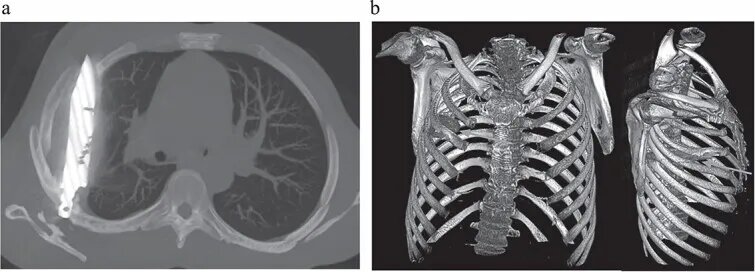

تصویربرداری با اشعه ایکس و سیتیاسکن نشان داد تیغهای بزرگ از چاقو از پشت قفسه سینه وارد شده، بین دندههای پنجم و ششم گیر کرده و نوک آن تا جلوی قفسه سینه بین دندههای سوم و چهارم امتداد یافته است. شکستگیهای ترمیمشده در استخوان کتف و چند دنده نیز مشاهده شد. همچنین اطراف تیغه، بافت مرده و چرک تجمع یافته بود.